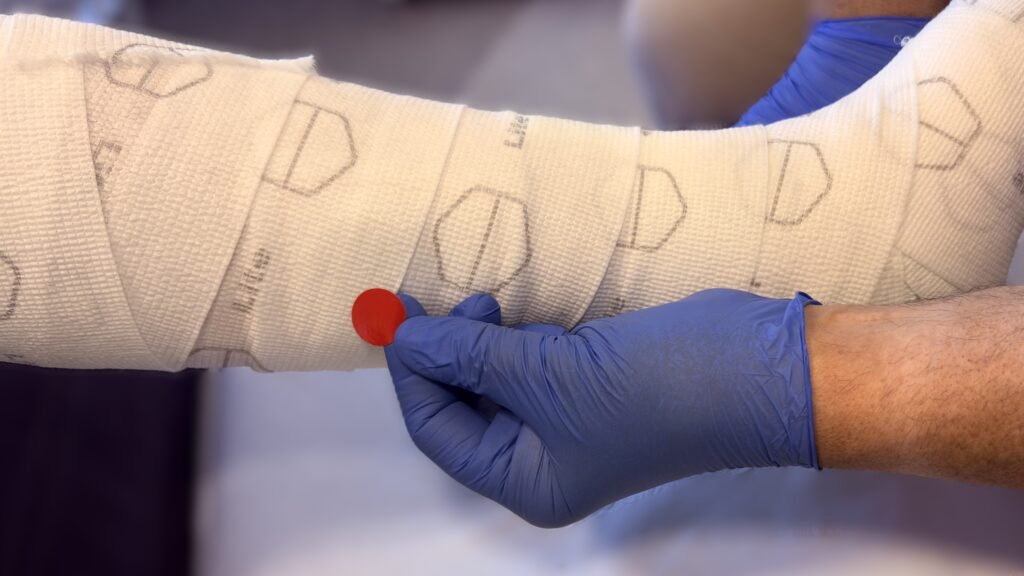

![]() Video: Alginate als Wundfüller

Video: Alginate als Wundfüller